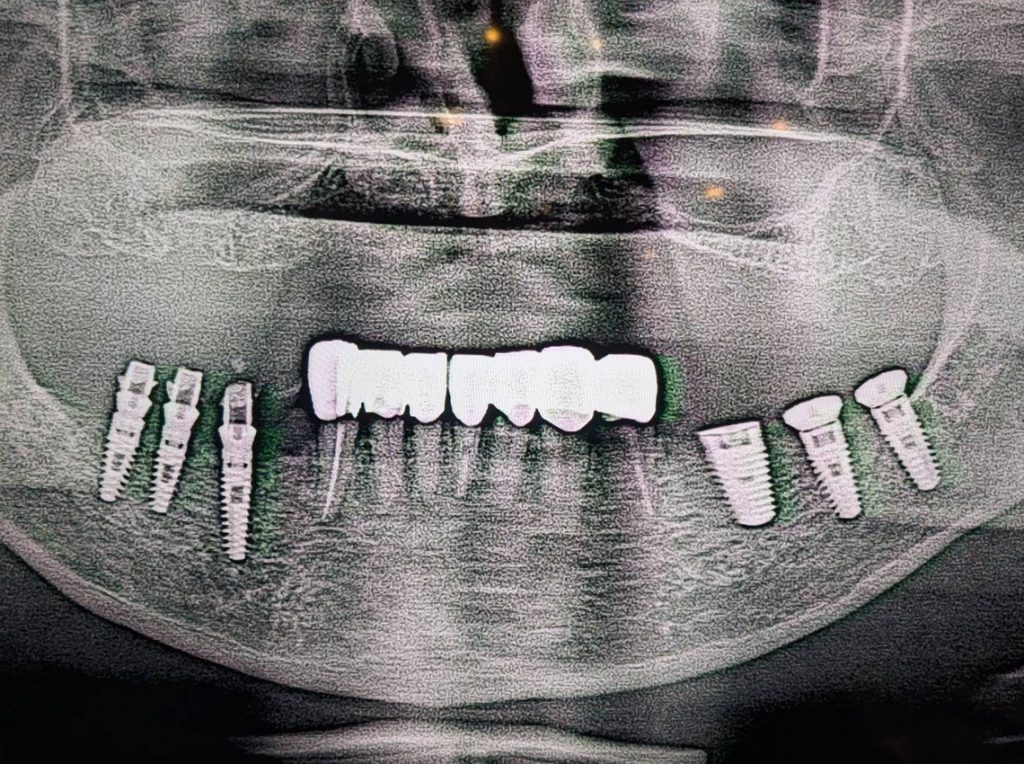

左右の大臼歯にインプラントを埋入しました。これにより、しっかりと力を受け止める土台が完成しました。